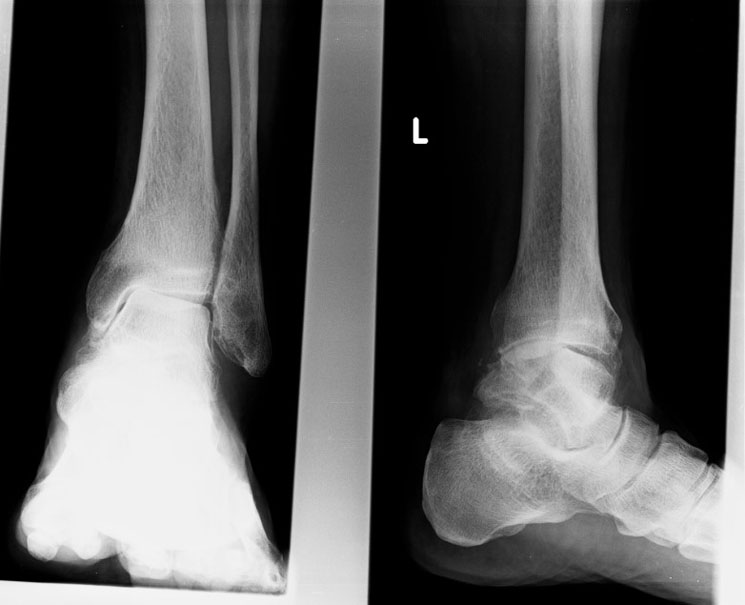

From radiopaedia.org

Severe osteoarthritis of the ankle Image Arthritis In Ankle Bone Symptoms The most common foot and ankle arthritis symptoms include: The pain may come and go or be low level and. Ankle arthritis affects the tibiotalar joint, which. This article will go over what you should know about ankle osteoarthritis, including the symptoms of ankle osteoarthritis, how osteoarthritis in the ankle is diagnosed, and treatment for ankle osteoarthritis. Reduced motion, such. Arthritis In Ankle Bone Symptoms.